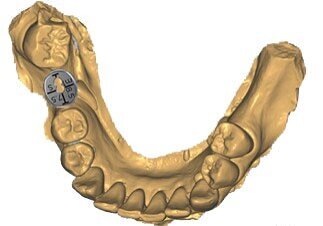

In questo caso particolare abbiamo eseguito una impronta digitale prima del trattamento chirurgico con un dispositivo di scansione intraorale e un file STL è stato inviato al tecnico di laboratorio. Lo scopo del flusso di lavoro digitale adottato qui era di progettare digitalmente e preparare l’unità di profilo personalizzato e un template come guida per il taglio della barriera lamellare con i seguenti processi:

Il file STL è stato prima importato nel software exocad (Fig. 16). Successivamente, è stata selezionata e importata nel software una tabella digitale VPI Cervico adatta al sito e allo spazio interprossimale (Fig. 17). Un’unità di profilo corrispondente all’abbinamento digitale della tabella è stata progettata dopo la scansione del modulo VPI Cervico con un dispositivo di scansione Ceramill Map 400 (Amann Girrbach) e posizionata 3 mm al di sotto della gengiva sul modello exocad. Il design è stato inviato all’operatore e, dopo la sua approvazione, è stata creata una scanalatura di 1 mm di larghezza e 0,5 mm di profondità a livello della mucosa marginale utilizzando gli strumenti di exocad (Figg. 18, 19). Il profilo è stato quindi stampato con una stampante 3D Asiga 3D max utilizzando una resina free print temp A2, pulito con alcool isopropilico al 99%, post-indurito utilizzando Otoflash G171 con azoto e infine rimosso dalla sua struttura di supporto e pulito con un vaporizzatore (Fig. 20). Questa unità di profilo è stata collegata in bocca durante l’intervento chirurgico con il cilindro temporaneo per generare un moncone personalizzato. Sono state aggiunte estensioni mesiali e distali occlusali ai denti vicini 45 e 47 all’unità al fine di facilitarne il posizionamento e l’adattamento all’interno del cilindro provvisorio.

Fig. 18_Scelta della tabella digitale VPI appropriata sul modello Exocad.

Fig. 19_L’unità di profilo con la scanalatura di trattenimento a livello della mucosa marginale generata con gli strumenti di Exocad.

Fig. 20_L’unità di profilo personalizzato prima del suo collegamento con il cilindro provvisorio.